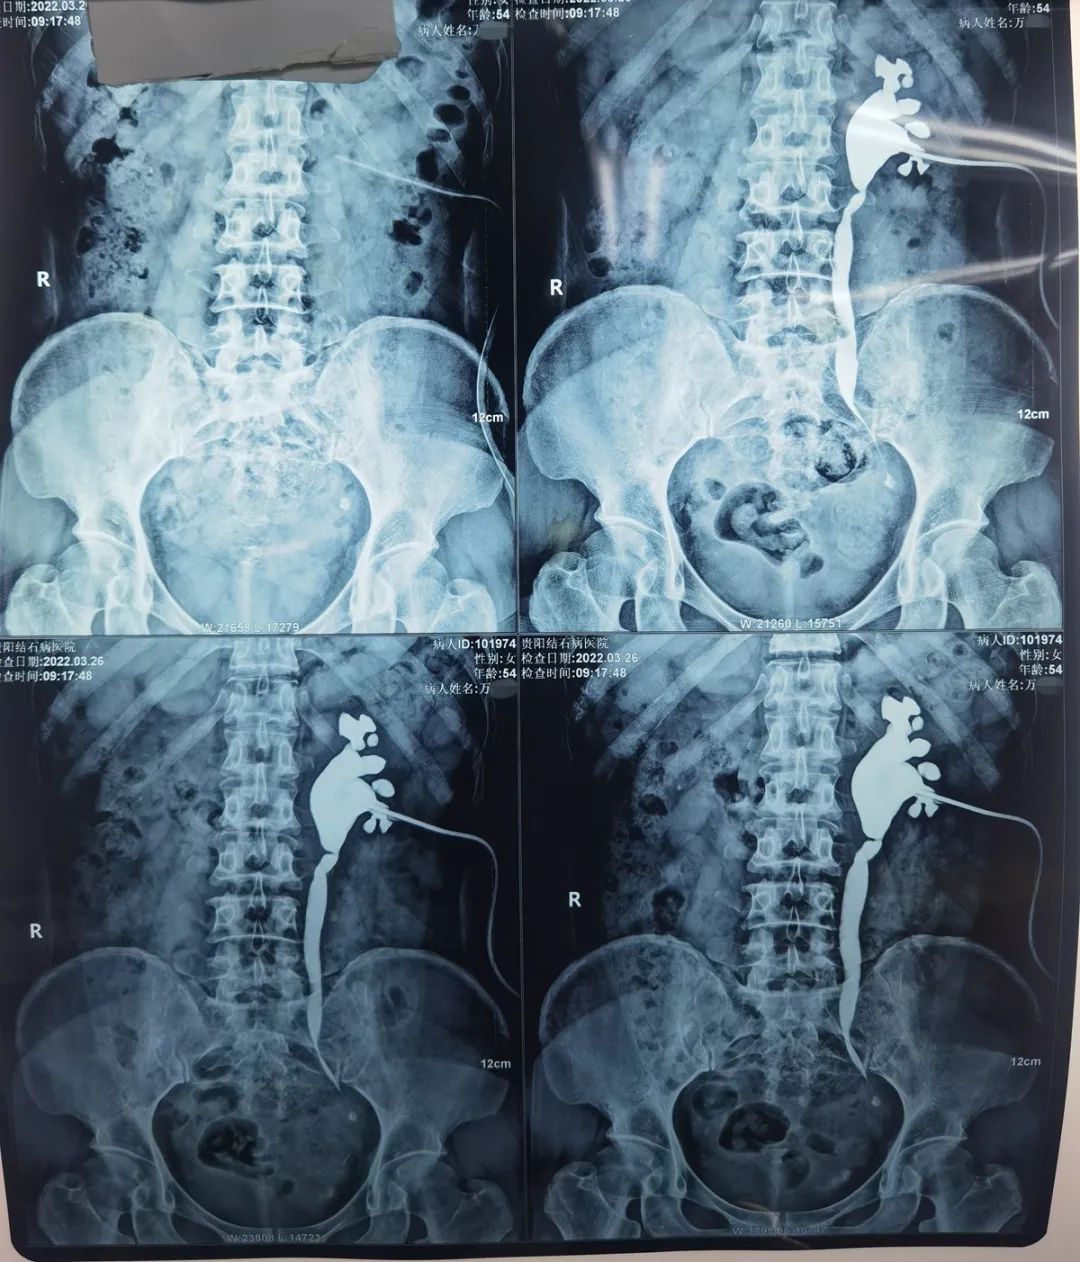

患者术前检查的X光片